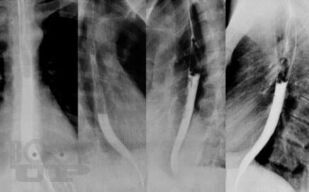

В книге изложены основные сведения по анатомии и патофизиологии пищевода и кардии, освещены вопросы клиники, диагностики, консервативного и оперативного лечения их хирургических заболеваний. С учетом последних достижений медицинской науки и практики описаны нервно-мышечные заболевания пищевода, гастроэзофагеальная рефлюксная болезнь, злокачественные новообразования, травмы, ожоги, болезни оперированного пищевода. Особое внимание уделено хирургической тактике и технике оперативных  вмешательств.